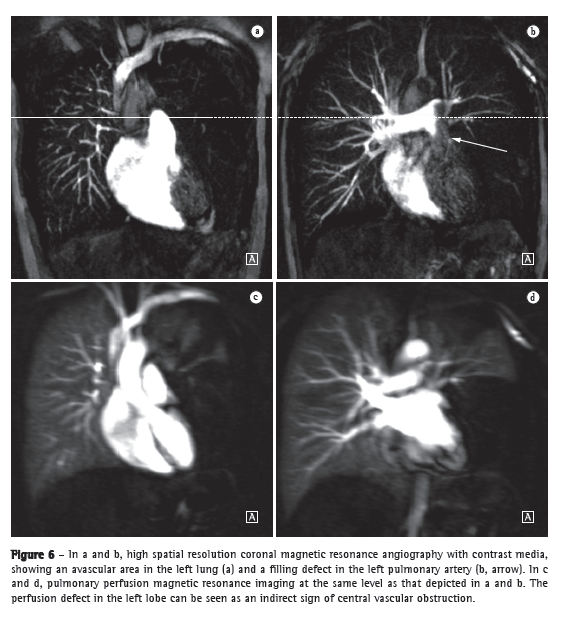

Substantial technical advances in pulmonary MRA have been introduced in recent years (Figures 5 and 6). Continued improvements are ongoing and include the use of parallel imaging, view sharing, time-resolved echo-shared angiography,(17-19) and pulmonary perfusion. These techniques have shortened MRA acquisition time, made it less susceptible to motion artifacts, and improved spatial resolution. One study showed that a combined magnetic resonance protocol (progressing from real-time MRI to perfusion MRI to MRA) is reliable and sensitive, producing results similar to those obtained with 16-slice multidetector CT.(18)

In 2003, Stein et al.(20) conducted a meta-analysis of the use of gadolinium-enhanced MRI for the depiction of acute pulmonary embolism. The authors used conventional pulmonary angiography as the reference standard. They found that the reported sensitivity of the procedure covered a broad range (77-100%) and that the reported specificity was uniformly high (95-98%).(20) In the most recent of the studies evaluated in that meta-analysis, Oudkerk et al.(21) showed that the sensitivity of contrast-enhanced MRI for pulmonary embolism was 100% in the central and lobar arteries; 84% in the segmental arteries; and only 40% in the subsegmental branches.

In cases of suspected acute pulmonary embolism, MRI with a state-of-the-art, three-component protocol (true fast imaging with steady-state precession; perfusion; and MRA with parallel acquisition) has recently been shown to be highly accurate.(18) The reported per-patient sensitivity and specificity, respectively, are 85% and 98% for the true fast imaging sequence; 100% and 91% for the perfusion sequence; and 77% and 100% for the MRA. The combined protocol has a reported sensitivity of 100% and a reported specificity of 93%. Although MRI and MRA are specific, they have low sensitivity, particularly for subsegmental pulmonary embolism. Overall, the combined MRI protocol has been found to be more reliable and sensitive than is 16-slice multidetector CT.(18) The average MRI examination time is reported to be approximately 10 min.(18)